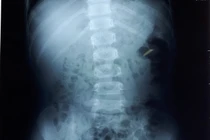

Qua thăm khám, làm siêu âm hệ niệu và X-quang bụng, các bác sĩ khoa Ngoại Thận – Tiết Niệu – Nam Học BVĐK Tỉnh Bắc Giang phát hiện nhiều viên sỏi ở cả hai thận kích thước nhỏ 3mm và có 01 viên sỏi bàng quang kích thước 10mm nằm sát cổ bang quang cản trở đường ra của nước tiểu đặc biệt ở tư thế đứng tiểu. Gia đình cháu L cho biết, rất ngạc nhiên vì nghĩ cháu bé như vậy thì không thể có sỏi thận được.